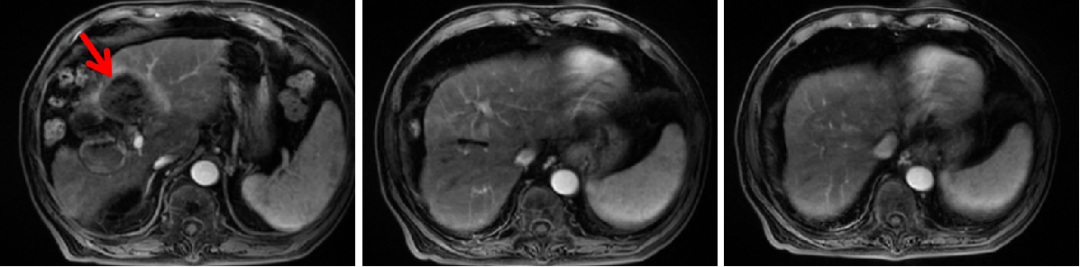

患者经过四次介入治疗后,复查提示存活病灶范围明显增大、肝内新发多发病灶、AFP明显升高,考虑病情未得到有效控制,遂来我科就诊。经患者充分知情同意并签署知情同意书后,分别于2020年4月2日、2020年4月28日、2020年5月19日、2020年6月16日、2020年7月7日予以免疫联合治疗方案:替雷利珠单抗200 mg q3w ivgtt + 仑伐替尼8 mg qd po。

腹部CT(2020-06-12):肝IV段病灶较前(2020-03-13)进一步缩小、坏死。

AFP:已降低至正常(8.5 ng/ml)。

疗效评价:CR(mRESIST)。

无进展生存期(PFS):超过4.4个月。

图4:2020年6月12日,免疫联合治疗3周期后腹部CT